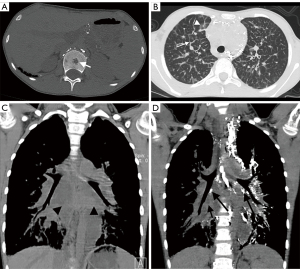

A total of 11 cases underwent CT-enhanced scans of the chest and abdomen, and no enhancement was seen in any of the osseous lesions. The extraosseous lesions of 39 cases are shown in Table 3, Figures 6,7, and the abnormal distribution of lipiodol in different extraosseous areas in CTL are shown in Table 4, Figure 7D, and Figure 8.

Previous literature has reported the CT manifestations of systematic lymphatic abnormality-related osseous lesions include the following (4,23): (I) osteolytic lesions in the medulla and cortex with visible or invisible sclerotic margins; (II) no periosteal reaction in the lesioned bone; (III) no vascular penetration within the lesion; and (IV) swelling of the soft tissue adjacent to the affected bone but no soft tissue mass formation. All 39 cases had lesions involving cancellous bone with or without sclerotic margins in this study, and no periosteal reaction was seen. No enhancement within the lesions on enhanced CT was seen in 11 cases, which could exclude vascular-related lesions, and 25 patients had extraosseous soft tissue hyperplasia and swelling, which is consistent with literature reports. Lipiodol deposition within the lesions shown in CTL is a characteristic manifestation of systematic lymphatic abnormality-related osseous lesions, which has not been reported in the literature. In this study, based on the density and morphological characteristics of the lesions, four types of systematic lymphatic abnormality-related osseous lesions were classified: cyst-like, duct-like or honeycomb-like, osteoporosis-like, and osteosclerosis-like. Among them, lipiodol deposits were seen in only one of the lesions with cystic changes, which was considered because: (I) the lesion did not communicate with the lymphatic vessels; (II) the waiting time after direct lymphangiography was short, and lipiodol had not yet entered the lesion. The extraosseous manifestations of CTL are suggestive for the diagnosis of systematic lymphatic abnormality-related osseous lesions. In our study, extraosseous lymphatic abnormalities were seen in all 39 patients, including lymphangiectasia, celiac disease, small bowel lymphangiectasia, and abnormal distribution and reflux of lipiodol in various extraosseous sites.